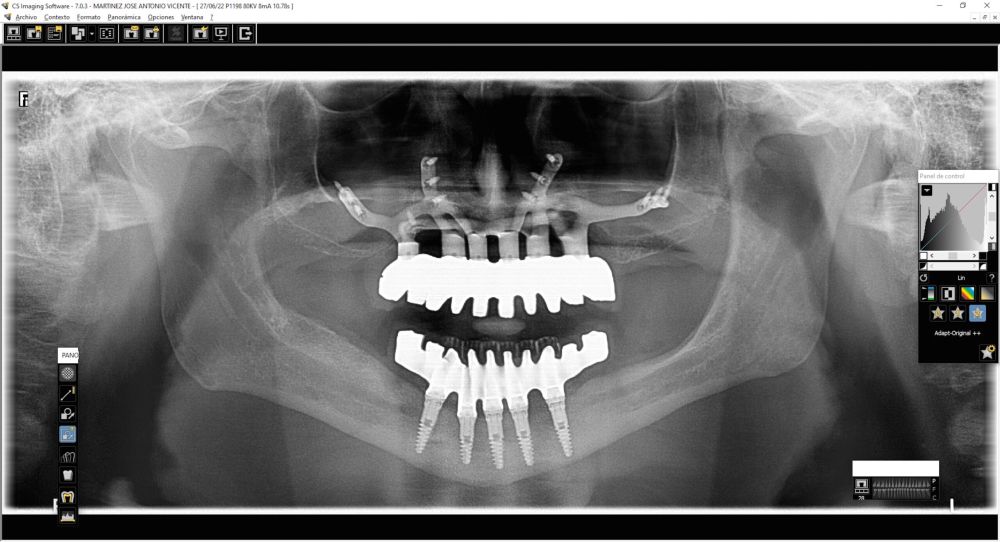

We present the clinical case of a 65-year-old patient with an implant-supported dentoalveolar rehabilitation on implants in the upper arch, placed in 2010, on which he referred pain, mobility and suppuration. After an orthopantomography, we observed a severe generalised perimplantitis in the upper arch, affecting all implants (Figure 1). It was explained to the patient that it was not possible to perform a bone regeneration of the lost tissues.

For this purpose, intraoral photographs were made and the complete prosthesis of the patient was used for the different planning tests. First, the double scanning technique was used, adding different radiopaque markers with gutta percha in the prosthesis10 (Figure 3). Then, the scanning was obtained with a conical beam computerized tomography (CBCT), (Planmeca ProMax 3D, Helsinki, Finland), both the prosthesis and the patient with his prosthesis stabilized with a silicone bite registration (Figure 4). In addition, an intraoral scan of the patient’s prosthesis was performed. From this, a personalized structure was designed subperiosteal sintered in Titanium (Ti-6-4) (Custom 3D®) with 6 Multi-Unit® type connections (Branemark, Nobel Biocare) and fixed with osteosynthesis screws in the higher density and volume areas of the malar bone and upper jaw (Figure 5 and 6). At the same time, with the STL digital test of the planning of the mesh, and with the scanning of our complete prosthesis, the laboratory technician made an implantosupported rehabilitation milled in polymethylmethacrylate (PMMA) with Multi-Unit® type titanium interfaces for immediate loading (figures 7 and 8).